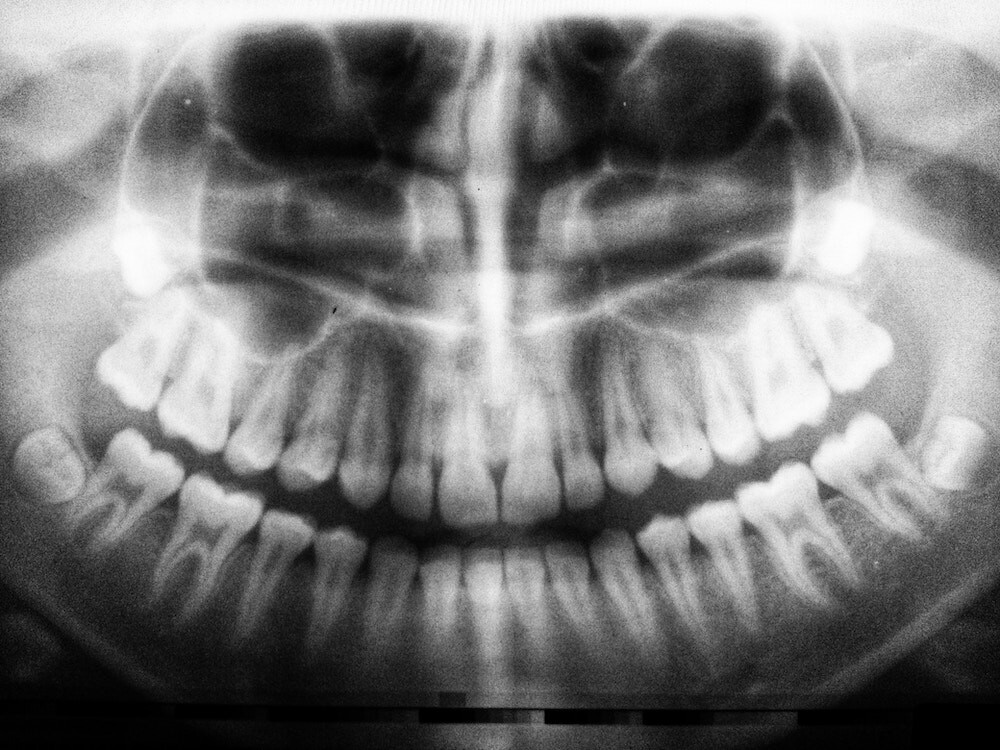

Bone Resorption: Why It Happens And What To Do Next

WHAT IS BONE RESORPTION?

Bone resorption is the biological process in which our bodies break down our bone tissue and release the minerals into our bloodstream. It’s a natural function that allows our bones to heal and renew themselves over time.

It’s a cycle of breaking down and regenerating — but the process can be interrupted when your body believes it no longer needs bone mass in that particular area. As a result, the bone gets broken down but not replaced.

One of the most common places for resorption to occur is in the jawbone.

WHAT CAUSES JAWBONE RESORPTION?

One of the main reasons for jawbone resorption is the loss of teeth.

When the root is removed, your jawbone no longer receives the stimulus and pressure of chewing. This causes your body to believe that it no longer requires the same bone density in that area.

When a tooth is extracted or lost, up to 25% of bone density can be lost in the first year — and the process continues. Jawbone loss causes your face to shrink, which may make you appear older than you actually are.